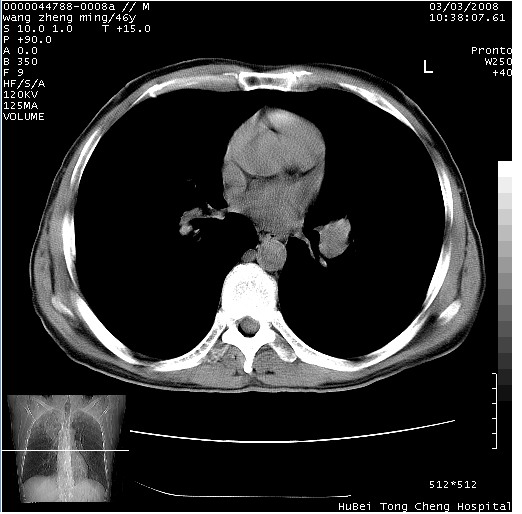

以下是引用卜一在2008-3-22 1:37:00的发言:[br]右肺实质性肿块,边缘不整,明显见毛刺征 分叶征及胸膜凹陷征,右上叶支气管明显变窄,远端散在的片状 斑片状实变影。另:左肺门较大肿块,支气管受累 变窄,远侧见阻塞性肺炎。纵隔内见肿大淋巴结。多考虑:右肺周围性肺癌伴左肺门 纵隔淋巴结转移!